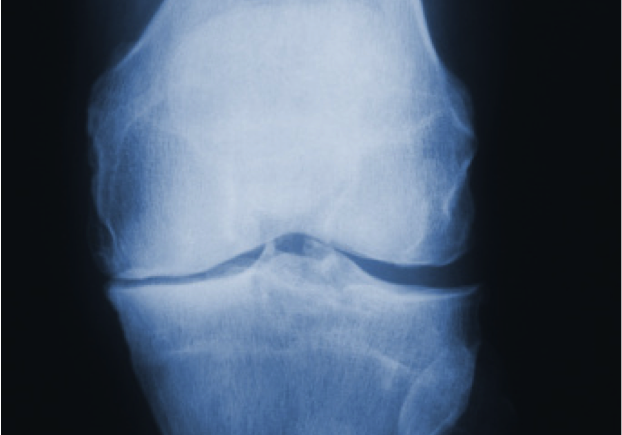

Reviewing options in osteoarthritis intervention

DePuy Synthes is a world leader in the provision of orthopaedic products which restore function and relieve pain for patients with serious joint conditions. With the incidence of osteoarthritis increasing, DePuy Synthes was seeking to strengthen its position in a specific segment of the market. As part of this initiative, DePuy Synthes asked Innovia to undertake a creative review of potential options.